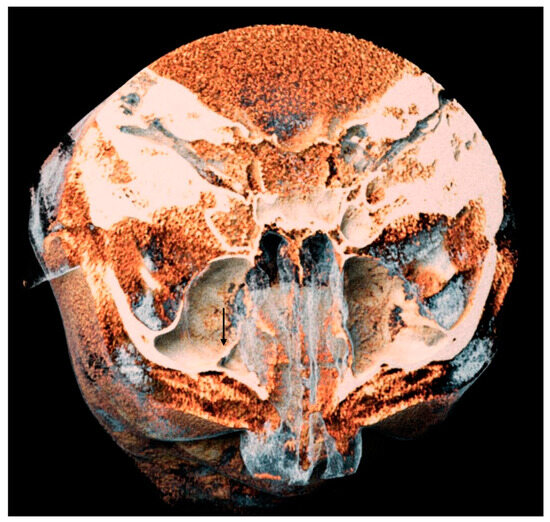

2.3. Evaluation of AAa

- The length of the arterial pathway in the mesiodistal dimension, on cross-section setting at 1 mm (Figure 2);

- The height of the maxillary bone crest in the cranio-caudal direction, on cross-section at the level of the first superior molar (Figure 3);

- The sized branches of the alveolar antral artery at the level of the first superior molar.